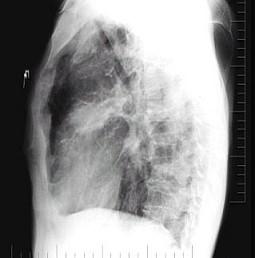

男性,72岁,感胸痛就诊,胸片检查如图,最可能的诊断是 ( )A.细支气管肺泡癌B.血行播散型肺结核C.肺转移瘤D.结核瘤E.胸腔积液

问题 男性,72岁,感胸痛就诊,胸片检查如图,最可能的诊断是 ( )

选项 A.细支气管肺泡癌 B.血行播散型肺结核 C.肺转移瘤 D.结核瘤 E.胸腔积液

答案 C